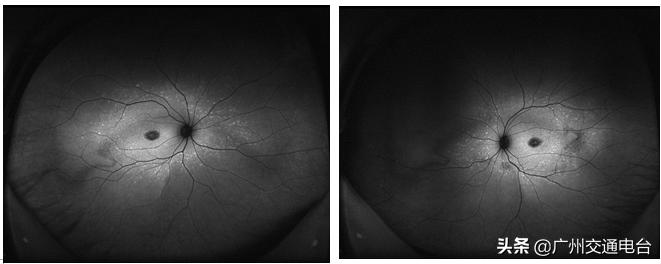

广州爱尔眼科医院大视光与近视防控科副主任张晓晓接诊后,用超广角的眼底检查设备为小海进行了一次详细的检查。检查发现,小海眼底黄斑的正常结构已经消失,取而代之的是一个像“靶子”一样的萎缩斑,周围视网膜还有大量的黄色斑点,眼底造影检查也提示小海的黄斑已经严重萎缩。这些眼底改变都指向同一个结果:一种原发于视网膜色素上皮层的常染色体隐性遗传病,也叫Stargardt病。

▲欧堡FAF眼底照片,可见周围视网膜有大量黄色斑点,黄斑中心的反光消失。